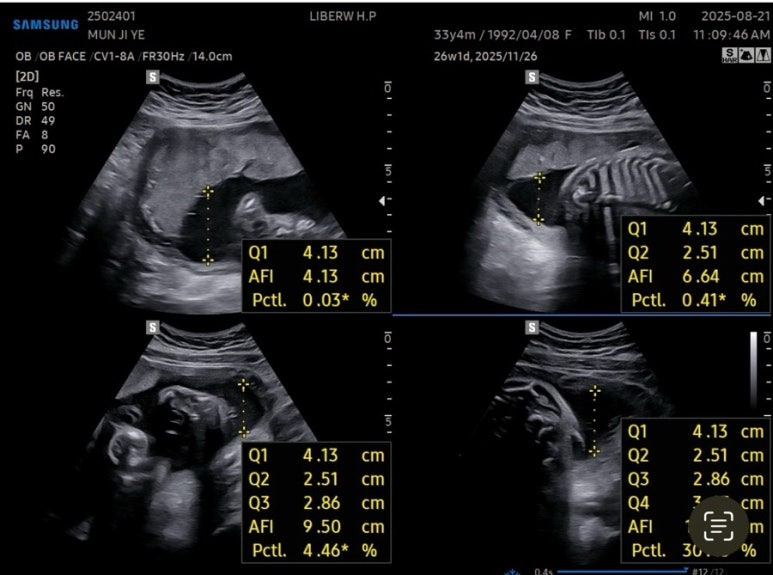

27주차 사탕이는

머리둘레 6.62cm

배 둘레 22.91cm

다리길이 4.61cm

몸무게 956g

심장박동수 150bpm

경부길이 3.44cm

양수량도 적당했다